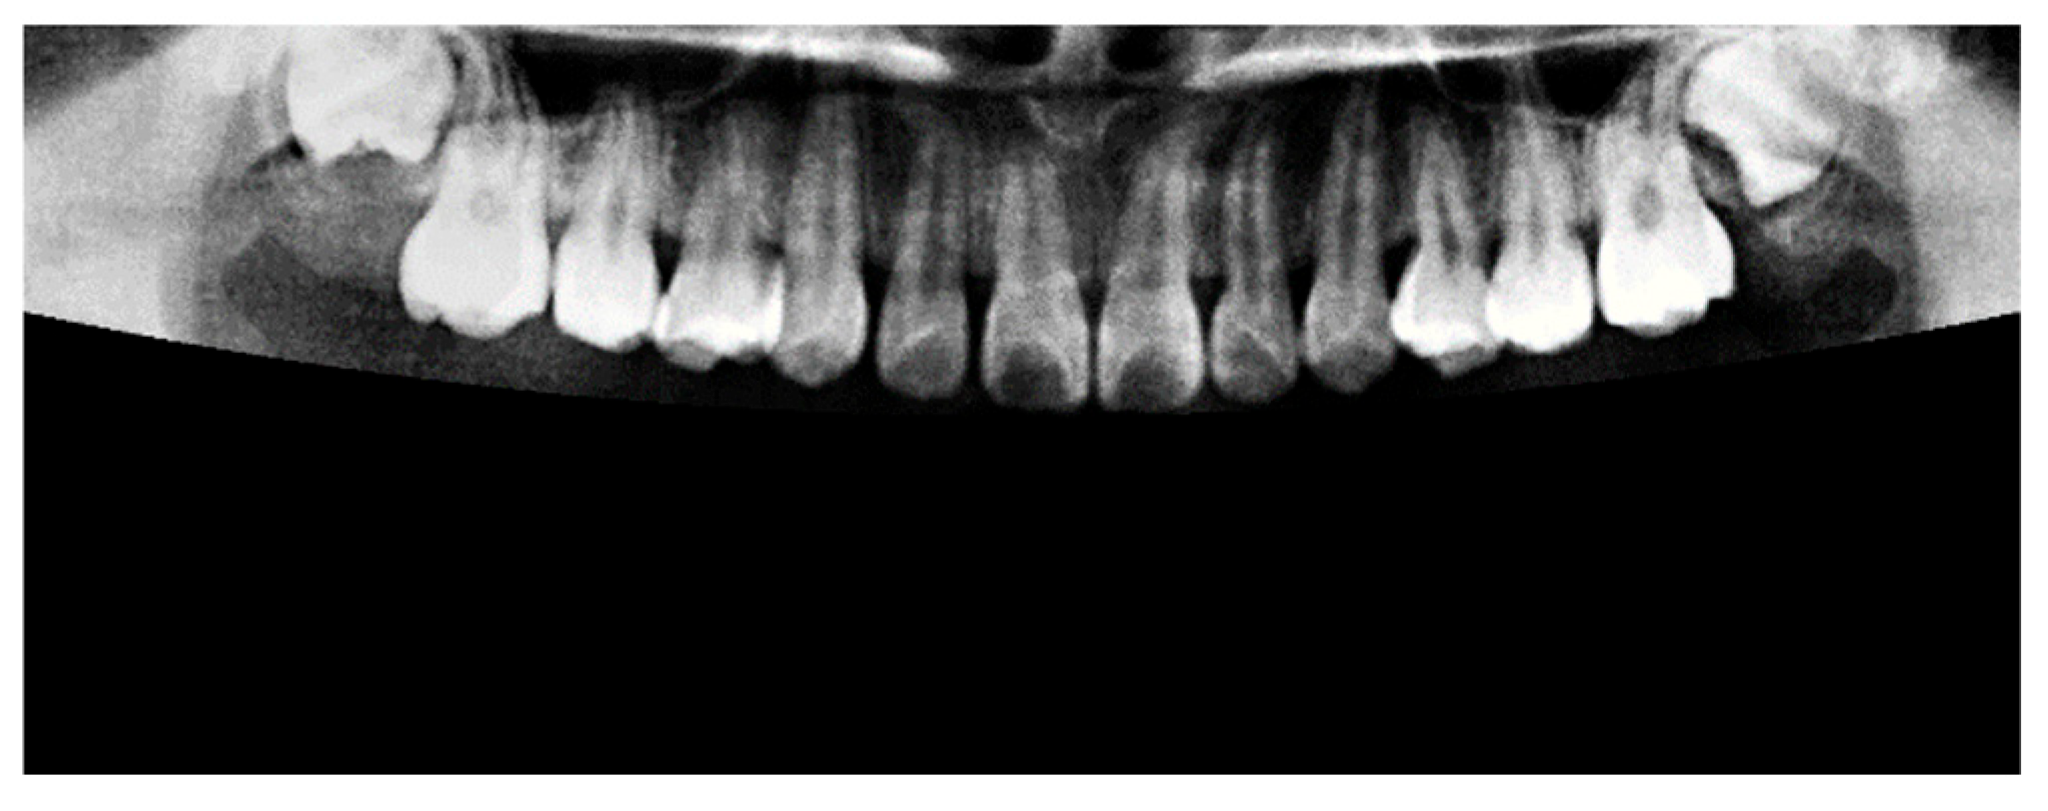

Insufficient brightness in the original PANO images may lead to inaccurate segmentation and hinder the extraction of relevant features. To mitigate this issue, background illumination was estimated and corrected using an opening operation from mathematical morphology [22], as defined in Equation (2). In this formulation, A x , y represents the original image and S i , j denotes a disk-shaped structuring element used in the morphological operation. The result of this illumination correction process is shown in Figure 5.

Figure 5. The result of image preprocessing through light adjustment.